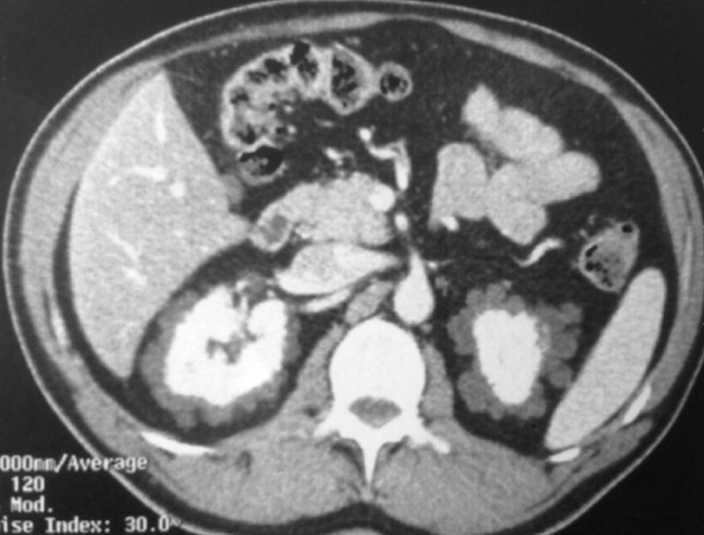

42) Now you are an expert in #kidney #cysts… can you guess what this patient has ?

43) Did you identify renal #lymphangiectasia ? Well done ! Don’t miss this specific finding of benign perirenal cystic appearance.